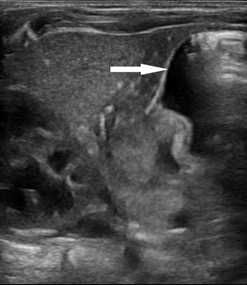

患儿女,33天,足月儿,因“反复严重呕吐30+天”于我院小儿外科门诊就诊,遂建议超声检查排除“先天性肥厚性幽门狭窄”。超声所见:十二指肠呈空虚状态。幽门壁肌层最厚约4.4mm,幽门最大横径约14mm,幽门管长约19mm(图1-3),幽门管腔变窄,胃内查见液性及稍强回声潴留物,胃内容物通过幽门管受阻(图4)。超声诊断为“先天性肥厚性幽门狭窄”。遂入院手术治疗,术中及术后病理证实为CHPS。

图2:幽门横断